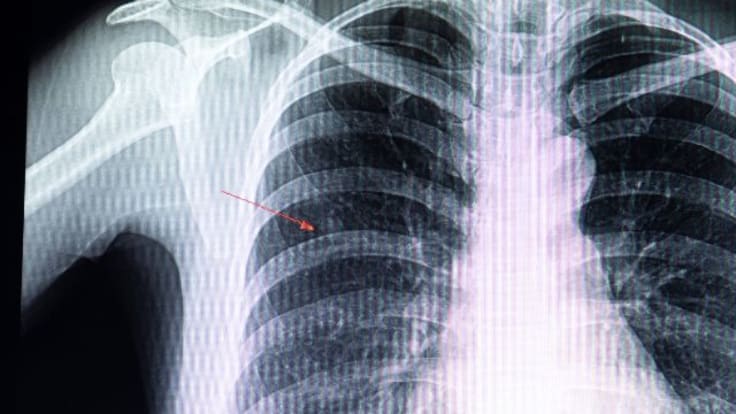

Certains nodules correspondent à des tumeurs non agressives et sans danger. Toutefois, la présence de nodules peut également révéler un cancer du poumon. Parfois, ils témoignent de la propagation d’un cancer provenant d’un autre organe, comme le sein ou le côlon, sous forme de métastases. C’est pourquoi les médecins s’attachent à identifier précisément la nature du nodule détecté, notamment à l’aide d’une radiographie ou, de manière plus fiable, grâce à un scanner.

Un nodule est une masse souvent solide de forme arrondie, constituée de cellules et/ou de tissus. Lorsqu’il se situe sous la peau, il peut parfois être perçu au toucher. Cependant, s’il est localisé plus en profondeur, comme dans les poumons, il reste indétectable par palpation. Selon sa taille, il peut être mis en évidence lors d’un examen d’imagerie médicale, tel qu’une radiographie ou un scanner, et souvent découvert de manière fortuite. Bien que la majorité des nodules soient bénins et constituent une anomalie fréquente chez l’être humain, certains peuvent révéler la présence d’une tumeur maligne.